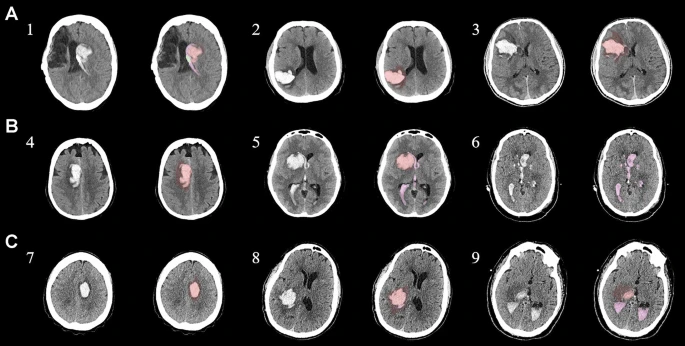

為了描述目的,患者按入組順序被賦予編號,并被連續分配到三組中的一組,每組三名。根據模型2分割,ICH體積范圍為0.1至54.9mL(平均ICH體積為23.5mL)。5名ICH患者受累于局限性腦葉,其余患者受累于基底神經節或外囊深處。3名患者的ICH位于丘腦(圖1),1名患者的血腫位于多個腦結構(即尾狀核、殼核和蒼白球)。平均而言,MSCs是在ICH后3天注射的。

結合臨床特征的探索性成像容積模型分析

ABC/2模型1和模型2分割方法均通過線性回歸顯示出ICH和IVH體積的良好相關性(圖3a、b)。與模型2分割體積方法(例如每CT15-20分鐘)相比,模型1ABC/2衍生的半定量方法和改進的Graeb IVH方法所需的時間更短(例如2-5分鐘)。有趣的是,將NIHSS評分與IVH體積M2方法進行比較顯示出線性相關性(R2=0.7217),并且當IVH小于20mL或大于20mL時,NIHSS評分似乎存在聚集性(圖3c)。PHE 分析顯示MSC注射劑量與PHE體積之間存在輕微的負相關關系。